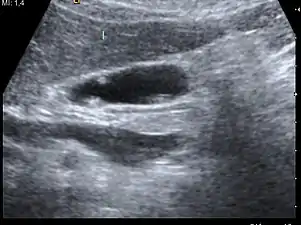

| A polyp in the gall bladder as seen on ultrasound |

Diagnosis is typically by ultrasound or CT imaging.

Ultrasound image of gallbladder polyps measuring 3–7 mm.